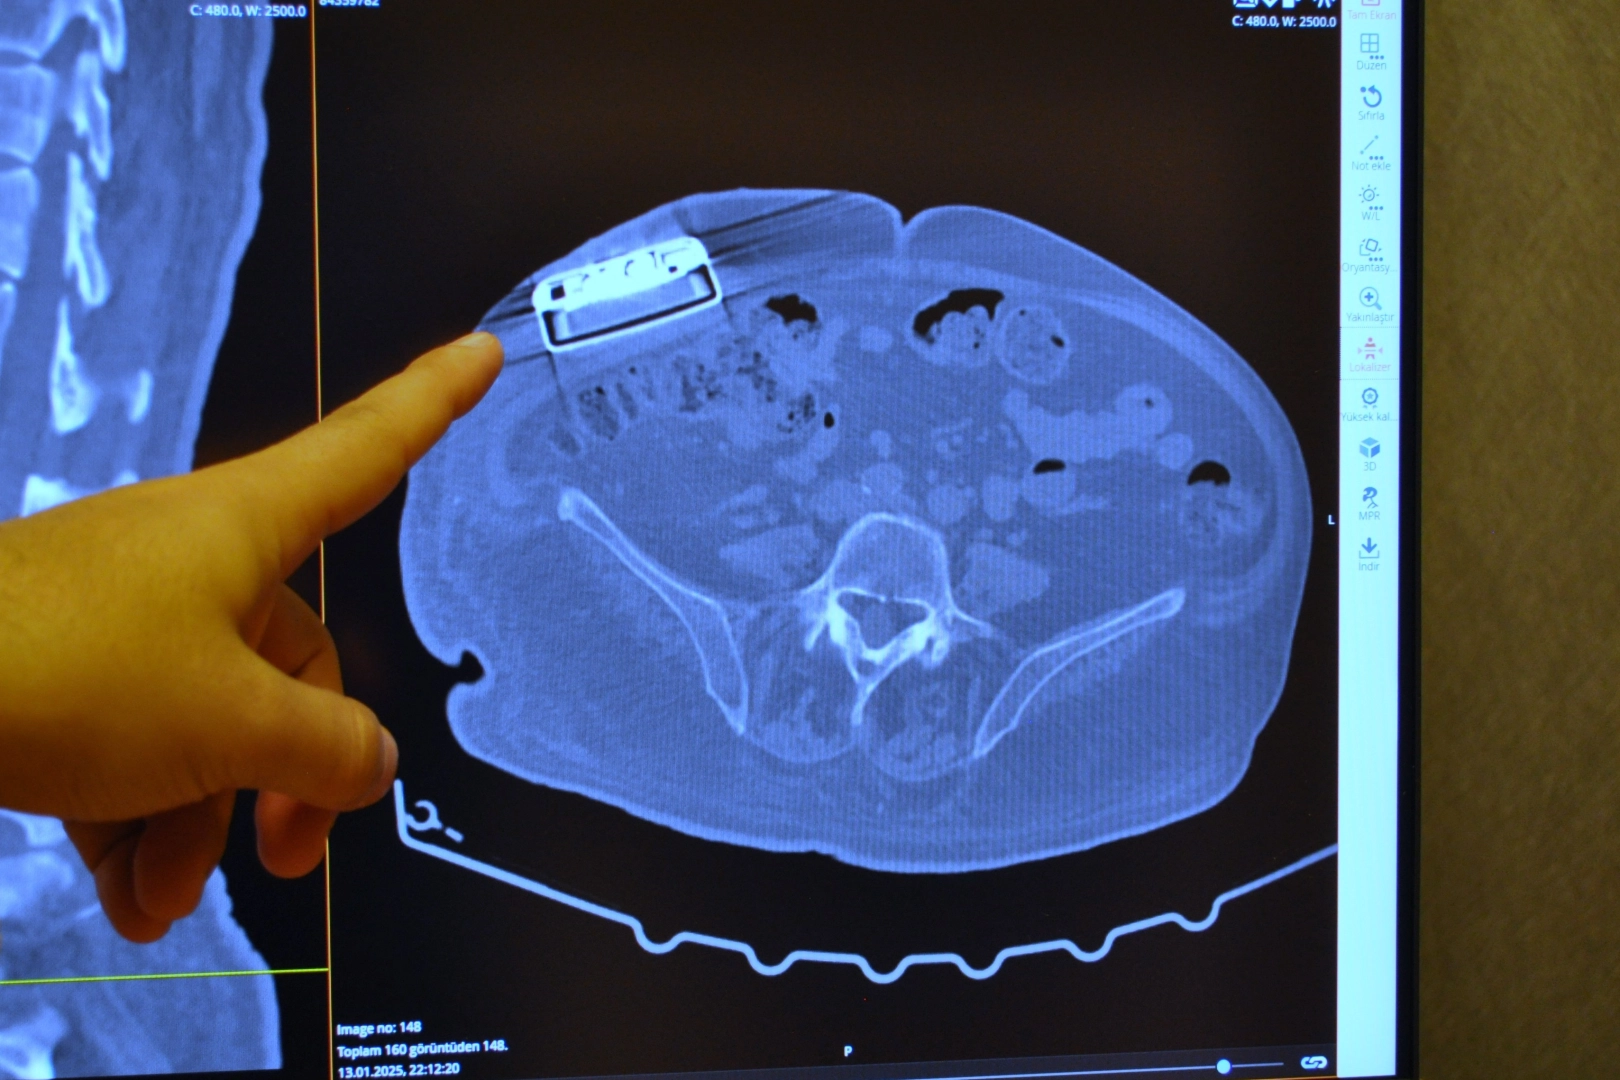

Operasyonla ilgili açıklamalarda bulunan Beyin ve Sinir Cerrahı Dr. Beşir Sürme, "65 yaşında erkek hasta, trafik kazasına bağlı bir omurilik hasarı geçiriyor ve bunun akabinde parapleji dediğimiz güç kaybı meydana geliyor. Gelişen bu omurilik hasarına bağlı hastada spastisite dediğimiz şiddetli kasılmalar oluşuyor ve hastaya baklofen pompası denilen bir cihaz implante ediliyor. Yaklaşık 11 sene önce implante edilen bu pompanın miadının dolması üzerine bize başvurdu ve biz bu hastamızda bir pompa değişimi ameliyatı gerçekleştirdik. Baklofen pompası tedavisi Türkiye'de daha önce de yapılan bir tedavi ancak biz yeni versiyon bir pompa yerleştirdik ve yeni özellikleri nedeniyle hastaya sağladığı özellikleri de gözlemledik" dedi.

Pompa tedavisinin daha önce uygulandığını ancak yeni teknoloji pompayı ilk kez erkek hastada kullandıklarını söyleyen Dr. Sürme, "Hastamızı yaklaşık 2 ay önce ameliyat ettik. Ameliyat sonrası programlamalarını yaptık. Bu hastalarda, hastalığın durumu ve hastanın ihtiyaçlarına göre verilecek ilacı pompa sayesinde programlayabiliyoruz. Programlamalardan sonra hastamız daha iyi olduğunu ve kasılmalarında belirgin düzelmeler olduğunu söylüyor. Hatta daha önceki pompaya göre şu an daha düşük doz ilaç vermemize rağmen hasta yine bundan fayda görebiliyor" şeklinde konuştu.